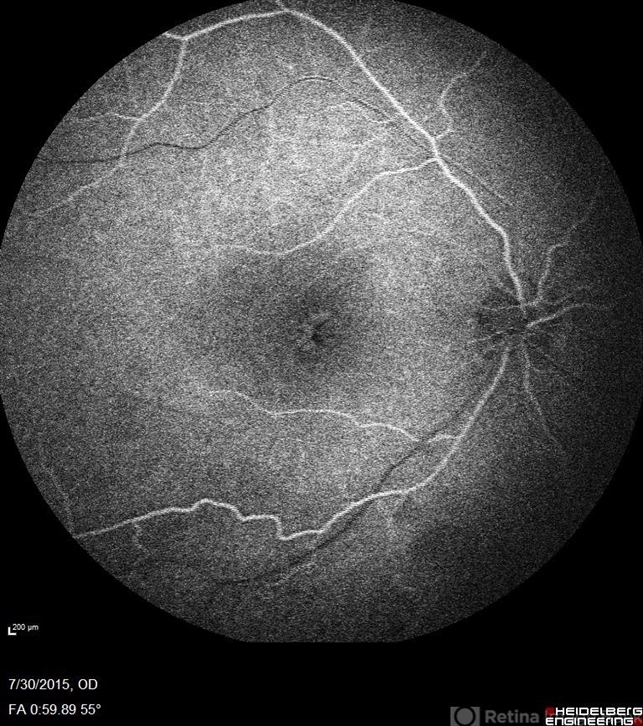

- Goldmann-Favre Syndrome, juvenile retinoschisis, retinal dystrophy

- Fluorescein angiography of a 24-year-old male. Juvenile retinoschisis on OCT. FA shows outer retinal staining. Could be associated with Goldman Farve Syndrome.